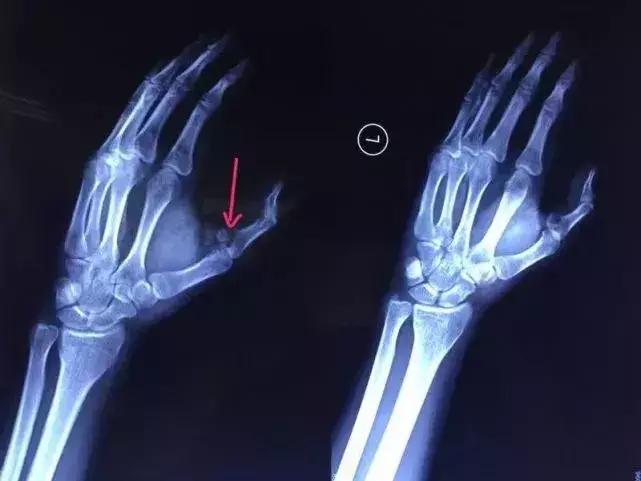

去到医院经过X光检查发现,小袁的左手拇指近节指骨骨折。当晚10点,医生给小袁进行手术,手术历时2小时顺利完成。术后,小袁的左手需采用石膏固定4~6周。

X光检查发现,左手拇指骨折。(箭头所示)▲